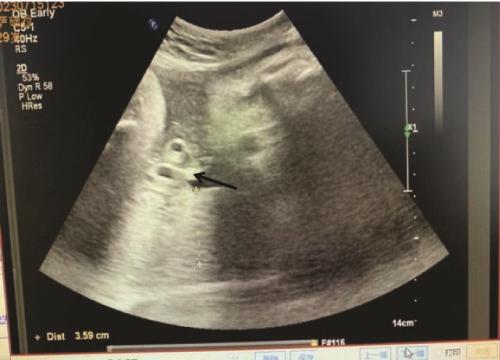

Objective: To analyze the clinical profiles of parturients with umbilical vascular thrombosis, to delineate early recognition markers and diagnostic-therapeutic protocols, and to provide evidence for optimizing maternal-fetal outcome. Methods: Clinical data of 6 parturients with umbilical vascular thrombosis managed at Shenzhen Guangming District People's Hospital were retrospectively reviewed. Results: Among the 6 cases, 5 cases exhibited abnormal antepartum cardiotocography (CTG). Prenatal ultrasound identified umbilical vascular thrombosis in 3 cases, all delivered by emergency cesarean section promoted by pathological CTG patterns. Within this subgroup, one fetus presented with a secondary single umbilical artery and one with markedly tight umbilical cord spirals; the latter received a complete course of antenatal corticosteroids for fetal pulmonary maturation after sonographic detection of umbilical arterial thrombosis at 31+1 weeks, followed by emergency cesarean section at 34+4 weeks. In the remaining 3 cases, prenatal ultrasound revealed no umbilical vascular anomaly; 2 cases underwent emergency cesarean section for abnormal CTG and one had an elective cesarean section. All 6 neonates survived. Of the 5 parturient-neonate pairs screened for protein S and protein C activity, 4 mothers were deficient in protein S and 2 in protein C; 3 neonates were deficient in protein S and 5 in protein C. Conclusions: Whenever obstetric ultrasound indicates an altered umbilical vessel count, hyper-coiled umbilical cord, laboratory evidence of protein S or protein C deficiency, or abnormal CTG patterns, umbilical vascular thrombosis should be suspected. In preterm pregnancies with stable fetal status, expectant management under intensive surveillance may be considered.